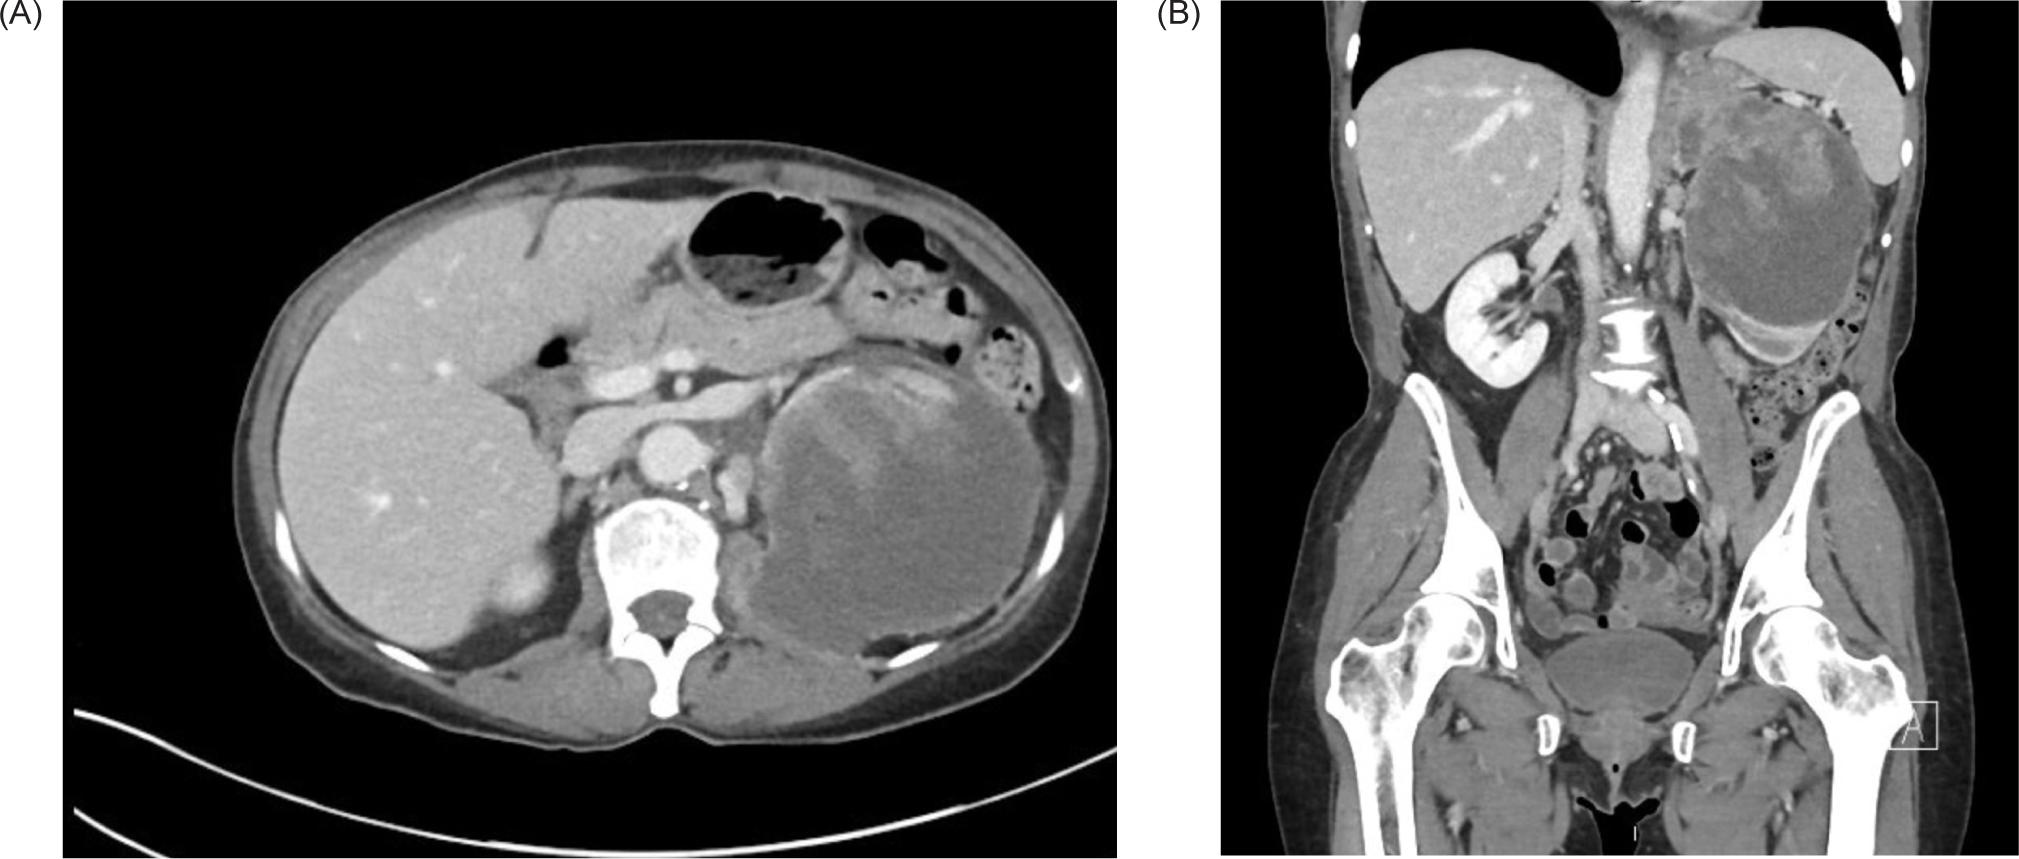

A 59-year-old female smoker with history of hypertension and hyperlipidemia who was screened for lung cancer with yearly low-dose CT scans was incidentally found to have a large left renal mass. Further evaluation via CT revealed a complex enhancing renal mass measuring 9.2.2 × 9.3 × 12.4 cm with extension into the left psoas muscle and abutting the pancreatic tail, spleen, and stomach (Figure 1). The patient underwent excision of a soft tissue mass, and surgical pathology was consistent with sarcoma. PET-CT scan revealed multiple avid lesions including lung nodules of up to 1.5 cm, a left adrenal mass, retroperitoneal adenopathy, and soft tissue metastases in the pelvic muscles as well as a lesion near the right atrium (Figure 2). An echocardiogram was performed in order to further evaluate the cardiac finding on the PET-CT scan, which revealed a 3.5 × 3.4 cm mass attached to the right atrial free wall, which was thought to represent a large thrombus or cardiac tumor, as well as a 0.75 cm mass noted on the atrial aspect of the IVC-RA junction likely representing the thrombus. Left ventricle ejection fraction was normal at 65%. The patient was instructed by her cardiologist to present to the Emergency Department for further evaluation given these findings. On presentation, the patient reported intermittent left flank pain, EKG was normal sinus rhythm with no acute ST changes, and CTA scan revealed likely invasion of perivascular nodules in the right upper lobe into subsegmental pulmonary arterial branches with associated pulmonary emboli within the distal subsegmental and more distal branches. The following day, cardiac MRI confirmed an intra-cardiac tumor occupying the entire right atrium with extension through the myocardium into the epicardial space and through the tricuspid valve into the right ventricle (Figure 3). MRI brain revealed three lesions consistent with metastatic disease. Renal biopsy was consistent with clear cell RCC with sarcomatoid features (Figure 4). Immunohistochemical studies were positive for desmin, PAX8, and myogenin, and negative for CK7. Patient was identified as poor risk per International Metastatic RCC Database Consortium (IMDC), with a median survival of 7.8 months. The patient received Ipilimumab and Nivolumab for one cycle, followed by Nivolumab only due to complication of diarrhea requiring steroid therapy. After three months of therapy that included three cycles of total therapy, she was noted to have partial response per Response Evaluation Criteria in Solid Tumors (RECIST) criteria. The patient will be continued on Nivolumab. The patient was also treated with gamma knife radiosurgery for her brain metastases.

Figure 1: CT of the abdomen and pelvis with IV contrast. (A) Transverse and (B) coronal views demonstrating a 9.2 × 9.3 × 12.4 cm left renal mass with extension into the left psoas.